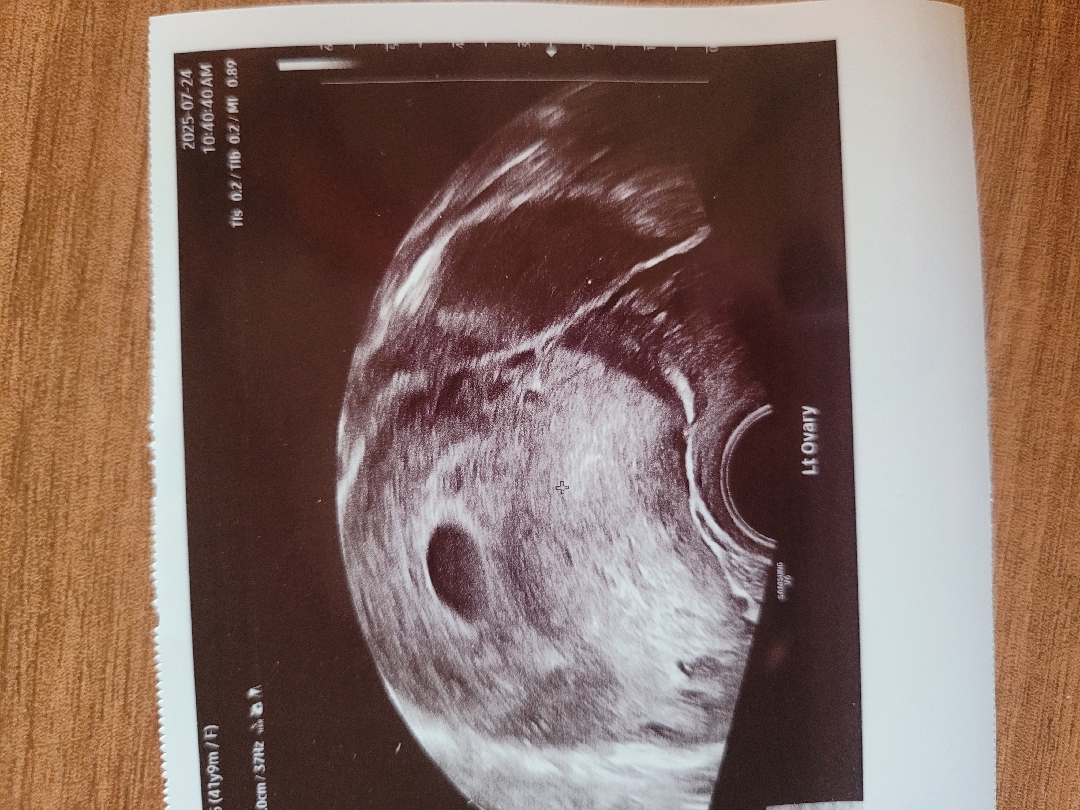

오늘초음파 보고왔어요

산부인과가서 오늘애기집확인하고 왔어요 6주인대 심소는 못듣고왔네요~